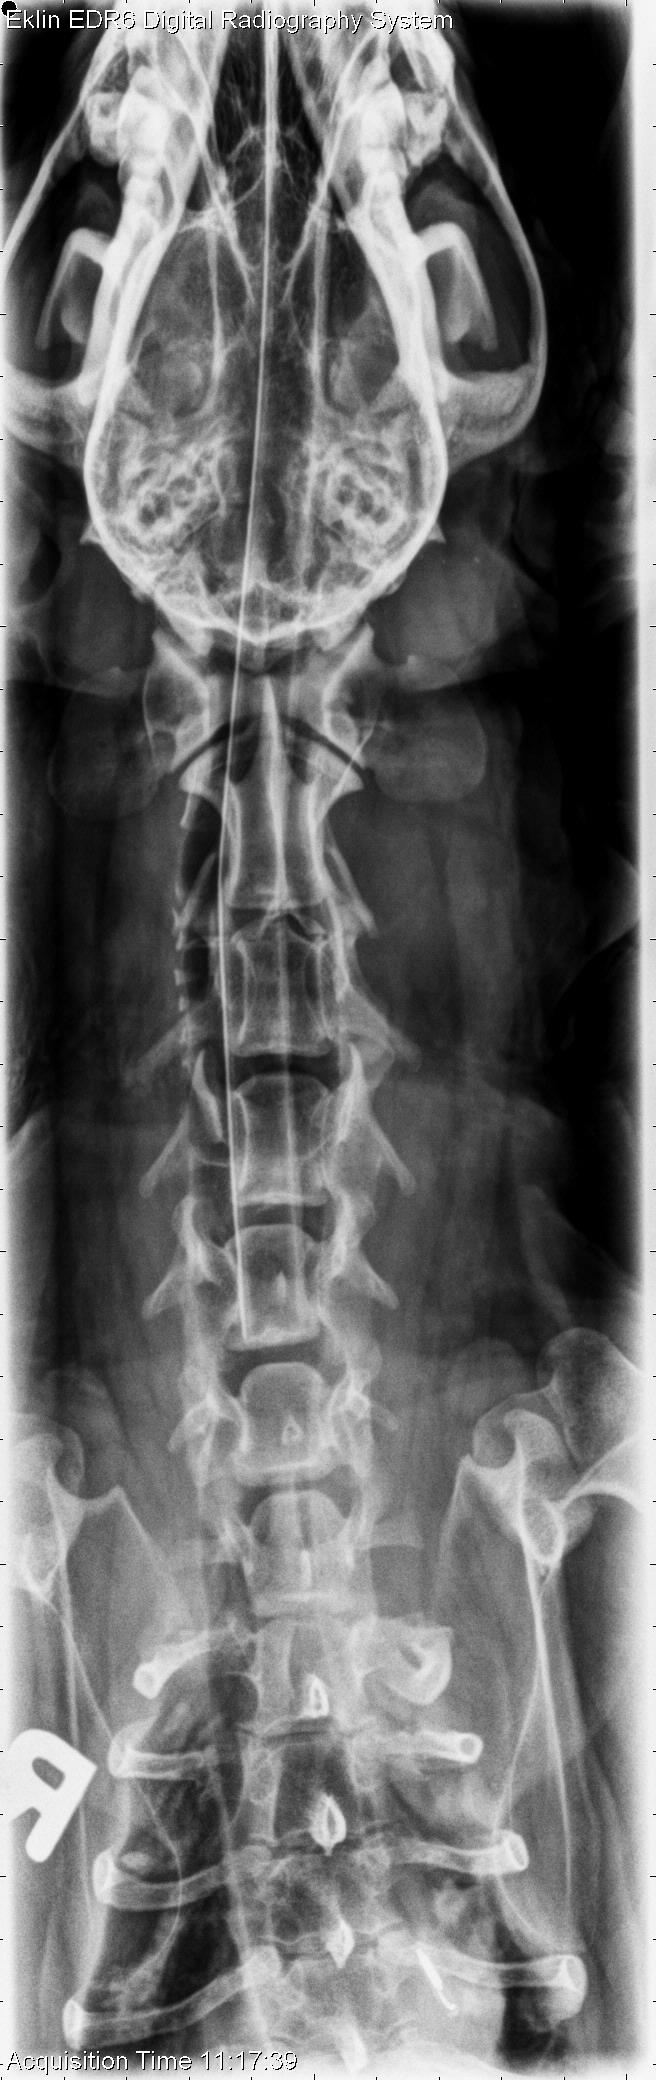

This week’s case is a 15-year-old female neutered Dachshund with several weeks history of non-ambulatory paraparesis. The tentative diagnosis is T3-L3 myelopathy. What are your findings?

On radiographs of the spine, there is scleroisis of the L6 vertebra most apparent on the lateral projection. On the ventrodorsal projection, there is loss of the cortical bone of the lamina at this level. The intervertebral foramen at L6-7 is irregular and enlarged. There is multifocal intervertebral disc space narrowing including T12-13, T13-L1, and L3-4, as well as spondylosis deformans throughout the spine.

The lysis and sclerosis of the L6 vertebra are consistent with an aggressive lesion, most likely neoplasia.

An MRI was performed, demonstrating a compressive mass in the L5-L7 region with spinal cord compression. Fine needle aspirate revealed malignant neoplasia, most likely sarcoma.